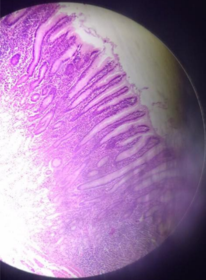

Small Intestine HE

Small Intestine - HE